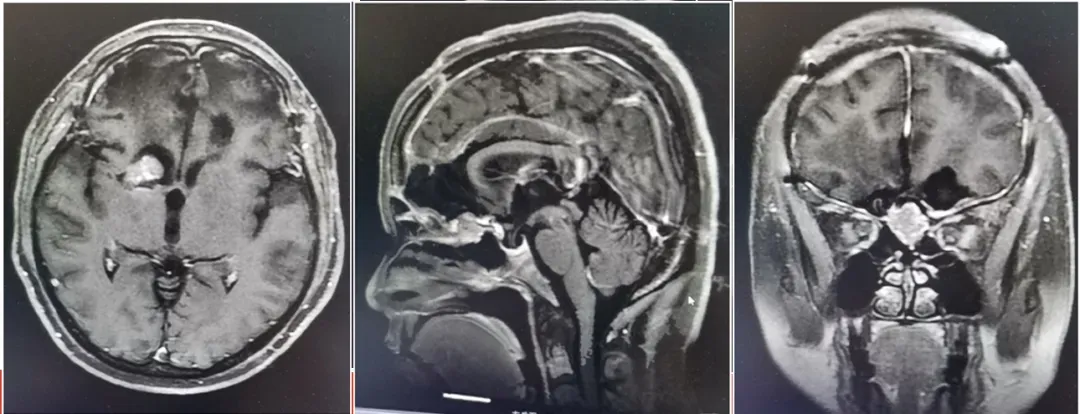

紧张的家庭氛围让付女士的家人忧心忡忡,后来发现付女士老是喊头疼,听人说起大脑健康问题也可能导致性格剧变,家人赶快带她来到神经外科就诊。医生给她做了个头颅 CT 检查,结果不做不要紧,一做可吓得够呛,付女士长了个“巨大的脑肿瘤”,和拳头差不多大小。经进一步核磁检查,确定是脑膜瘤,要手术切除。

西安长安医院神经外二科杨江河主任介绍到,“这个肿瘤长在大脑额叶部位,肿瘤的生长对额叶造成损伤,往往会导致患者出现性格改变,如偏执、易怒和情绪波动等。” 谜底揭晓,付女士一家的心结也终于打开,如何尽快帮助她恢复健康,成为一家人最迫切的愿望。

“脑膜瘤是较常见的颅内肿瘤之一,90%的脑膜瘤均为良性肿瘤。女性多于男性,中老年发病多见。很多病人在早期没有明显症状,出现症状的时间大多在肿瘤生长数年以后。”神经外二科杨江河主任介绍到,“大多数脑膜瘤无任何症状,多在检查其他疾病时偶尔发现。少数因肿瘤逐渐长大压迫脑组织,患者可能出现头疼、癫痫等症状,个别患者还可出现偏瘫、偏身麻木的表现。颅脑CT及MRI检查基本可以确定脑膜瘤的位置、大小、形态及与周围重要结构的关系。对于生长速度较慢、无任何症状、体积小的脑膜瘤,可不做特殊处理,定期观察即可,对于引起功能障碍的特殊部位的脑膜瘤,应及时行手术治疗,绝大多数患者能够手术治愈,预后良好。因此,对于检查发现颅内脑膜瘤的患者,不必惊慌,寻求神经外科医生的专业指导治疗至关重要。(唐婷)